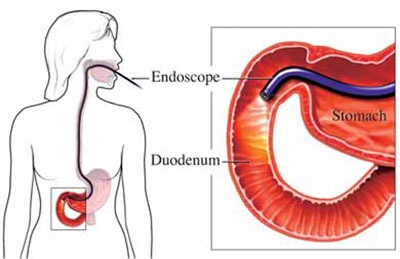

بیشتر بخوانید »علل،علائم و درمان واریس مری

واریس مری (به انگلیسی: Esophageal varices)، واریس عروق مری در قسمت انتهایی است که اغلب به دنبال سیروز پیشرفته کبدی و افزایش فشار ورید باب روی میدهد. واریس مری رگ های واریسی متورم در پایین مری که در اثر آسیب کبدی ایجاد می شود که با پارگی سبب خونریزی و به دلیل فشار بیش از حد خونریزی، این وضعیت یک …